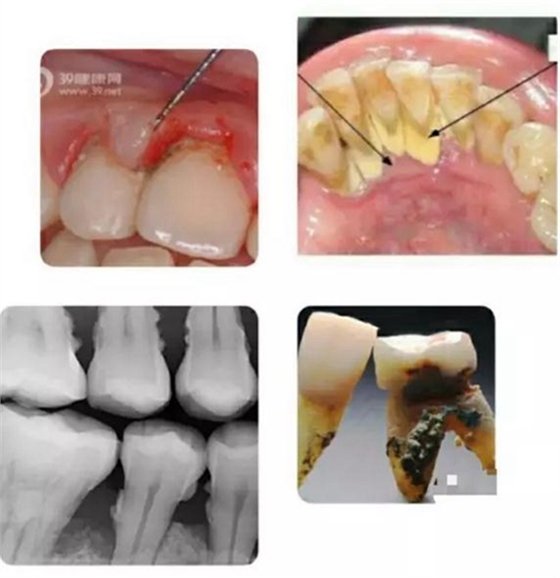

有圖有真相。上面這組圖片,自上而下從左至右,顯示了人類健康牙齒,患牙周病后,未加治療控制,以致病況越來越嚴重,最終牙齒逐漸脫落的過程。

如上圖所示,無論是肉眼直視,還是在X光片上顯現(xiàn),以及拔下的牙齒之上,牙周病患者的牙根面上都可見附著著大大小小的牙結(jié)石。

寄居在牙結(jié)石里的細菌可以釋放大量毒素,導(dǎo)致牙齦發(fā)炎,溶解,與牙面分離,從而突破牙槽骨保護的第一道屏障;繼而進一步直接使牙槽骨發(fā)炎,溶解,萎縮。若無牙科治療介入,牙槽骨可以被溶解殆盡,最終牙齒自行脫落。一般來講,牙齒上的牙結(jié)石越大越多,寄居的細菌就越多,牙周病就發(fā)展得越迅速越嚴重。

上列組圖大致列出了牙結(jié)石的成因: 首先是牙齒的復(fù)雜形狀與排列,形成有很多死角空間 ;其次是我們吃的食物會進入到這些死角空間里,而目前人們的刷牙工具和方法與各人刷牙的效果并不能保證所有食物殘渣被完全清除干凈。于是混合著口腔中天然存在的細菌,在舌肌頰肌唇肌等口腔周圍肌肉的擠壓下,殘留食物便緊粘在牙面上,并沉積了唾液中所含的鈣質(zhì)后,便形成了堅硬的牙結(jié)石,靠自己刷牙不可去掉。必須由經(jīng)過專業(yè)訓(xùn)練的牙醫(yī)或潔牙員使用專門工具才能清除。